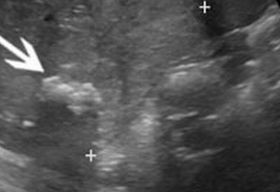

A Wilms tumor a leggyakoribb gyermekkori hasi daganat. A daganat kiterjedésének megítélése céljából olcsó és gyors vizsgálat a hasi ultrahang. Pontos felmérésre a hasi, kismedencei CT illetve MR vizsgálat alkalmas. Szövettani mintavételre csak abban az esetben van szükség, ha az előzetes vizsgálatok alapján a daganat kiterjedése miatt műtétileg eltávolítása nem lehetséges.

Első jelét, a fájdalmatlan hasi szövetszaporulatot leggyakrabban a szülők észlelik. Az orvos általában tapintani tudja a daganatot a gyermek hasában. Ha felmerül a Wilms-tumor gyanúja, az elváltozás természetének és kiterjedésének meghatározása céljából ultrahangvizsgálatot, számítógépes rétegvizsgálatot (CT) vagy mágneses rezonanciavizsgálatot (MR) végeznek.

Elsőként általában hasi ultrahang készül, ha a szülő vagy orvos kitapintható duzzanatot észlel. Ezután CT vagy MR-vizsgálattal lehet pontosan meghatározni a daganat méretét és kiterjedését. Vér- és vizeletvizsgálatok is szükségesek az általános állapot felméréséhez, és műtét után szövettani vizsgálat is történik.